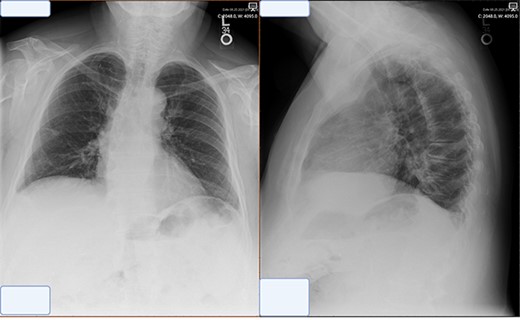

At the time of presentation to the pulmonologist, the patient was afebrile with a normal cardiopulmonary exam and vital signs. Chest X-ray revealed an enlarged right-sided heart border (Fig. 1). CT showed multiple sub-centimeter bilateral pulmonary nodules as well as a 6 x 2 cm right-sided pericardial cyst (Fig. 1). Further evaluation by MRI demonstrated gadolinium enhancement on T2 sequences with hypo enhancement noted on T1 sequences, confirming that the lesion was fluid-filled and cystic in nature.

Representative images of pericardial cysts on commonly employed imaging modalities. (A) The chest X-ray imaging of the patient described in the case report AP CXR showing widened mediastinum in a patient with a wide differential diagnosis which ultimately was found to be pericardial cyst. (B) CT imaging of the patient described in the case report with representative images of our patient demonstrating a sizeable pericardial cyst marked with red arrows and its close association with right phrenic nerve marked in gold. (C–E) MRI T1 (C) and T2 (D–E) appearances of pericardial cysts. Representative images of pericardial cyst appearance on gadolinium-enhanced MRI sequences. *Figure edited with BioRender.

Post-operative chest X-ray obtained at 2 week follow-up showing trace pleural effusion and otherwise normal X-ray.